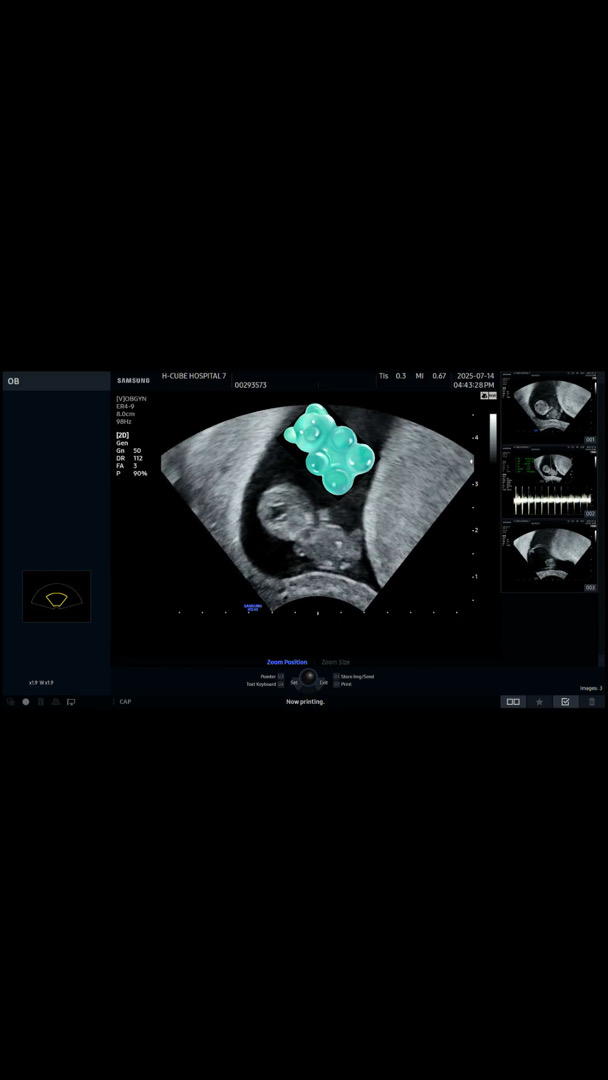

9주2일차 완벽한 젤리곰!

오늘 9주 1일차(애기 크기로는), 주수로는 9주 2일차 촘파 다녀왔어요 오늘 하루종일 일정땜에 점심도 못먹고 오후 4시꺼지 쫄쫄 굶고 넘 힘든데 애기 촘파 보고 내가 힘들게 해도 잘 있구나 잘컸구나 눈물이 펑펑나네요ㅠㅠㅜ호르몬때문이겠지만 눈물이 안멈춰요 대견한검지 미안해서인지ㅠ..

아뇨 9주2일차라 질촘파 봣구 담에 가면 배촘파 본다네용!!

2.2센치라던데 사람이 된다는게 넘 신기해요>.<ෆ